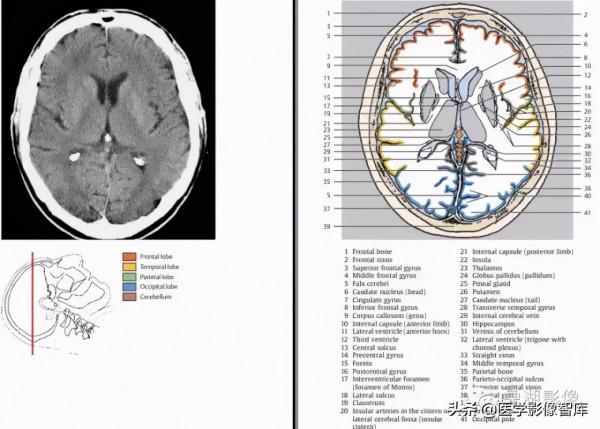

頭顱

1.額骨 2.額上回 3.冠狀縫 4.中央前溝 5.大腦鐮 6.中央前回 7.頂骨 8.旁中央小葉 9.中央溝 10.中央後回11.頂上小葉 12.楔前葉13.矢狀縫 14.上矢狀竇

1.額骨 2.上矢狀竇 3.額上葉 4.冠狀縫 5.大腦鐮 6.額中回 7.大腦縱裂 8.中央前溝 9.中央前回 10.中央溝 11.大腦白質(半卵圓中心)12.中央後回 13.旁中央小葉 14.緣上回 15.頂骨 16.頂下小葉 17.楔前葉 18.頂枕溝 19.枕骨

1.額骨 2.額上回 3.大腦鐮 4.額中回 5.扣帶回 6.冠狀縫 7.胼胝體周圍動脈 8.中央前回 9.放射冠 10.中央溝11.胼胝體 12.中央後回13.側腦室(脈絡膜叢) 14.中央後溝 15.頂骨 16.緣上回 17. 楔前葉 18.角回 19.頂枕溝 20.枕回 21.楔葉 22.枕骨 23.上矢狀竇

1.額骨 2.大腦鐮 3.額上回 4.額中回 5.額下回 6.扣帶回 7.胼胝體幹 8.側腦室前角 9.尾狀核頭10.中央前回 11.中央溝 12.放射冠 13.中央後回 14.屏狀核 15.丘腦 16.外側裂 17.顳葉島蓋 18.腦島 19.尾狀核尾 20.顳上回 21.胼胝體壓部 22.穹窿 23.扣帶回峽 24. 側腦室脈絡叢 25.直竇 26.大腦大靜脈27.頂骨 28.頂枕溝 29.枕回 30.楔葉 31.上矢狀竇 32.紋狀皮層(視覺初級皮層)33.枕骨

1.額骨 2.額竇 3.額上回 4.額中回 5.大腦鐮 6.尾狀核頭 7.扣帶回 8.額下回 9.胼胝體膝部 10.內囊前肢 11.側腦室前角 12.第三腦室 13.中央溝 14.中央前回 15.穹窿 16.中央後回 17.室間孔 18.外側裂 19.屏狀核20.外側裂池島動脈? 21.內囊後肢 22.島葉 23.丘腦 24.蒼白球 25.松果體 26.殼(核) 27.尾狀核尾 28.顳橫回 29.大腦內靜脈 30.海馬 31.小腦蚓部 32.側腦室后角(脈絡膜叢)33.直竇 34.顳中回 35.頂骨 36.頂枕溝 37.上矢狀竇 38.枕回 39.枕骨 40.紋狀皮層(視覺初級皮層)41.枕極

1.額骨 2.額竇 3.大腦鐮 4.額上回 5.扣帶回 6.額中回 7.胼胝體膝部 8.側腦室前角 9.內囊前肢 10.尾狀核頭11.頂骨 12.額下回 13.外囊 14.殼(核)15. 前聯合?16.外側裂池島動脈? 17.下丘腦 18.內囊膝 19.第三腦室 20.屏狀核 21.顳上回 22.外囊 23.顳骨 24.內囊後肢 25.膝狀體(內、外)26.內囊後肢 27.海馬28.丘腦 29.海馬旁回 30.松果體 31.小腦幕 32.四疊體板 33.小腦蚓部 34.四疊體池 35.直竇 36.顳中回 37.上矢狀竇 38.側腦室后角 39.枕骨 40.頂骨 41.枕回

1.額骨 2.額竇 3.大腦鐮 4.額上回 5.扣帶回 6.額中回 7.額下回 8.大腦前動脈 9.紋狀體(下部)10.外側裂(島池)11.島葉 12.島動脈 13.視束 14.顳上回 15.下丘腦 16.第三腦室 17.大腦腳 18.頂骨 19.側腦室(顳角) 20.腳間池 21.顳中回 22.海馬 23.海馬旁回 24.環池?25.中腦(四疊體板) 26.中腦導水管 27.顳下回 28.四疊體池 29.枕顳外側回 30.小腦蚓部 31.頂枕溝 32.小腦幕 33.上矢狀竇 34.直竇 35.枕骨 36.枕回

1.額竇 2.額骨 3.大腦鐮 4.眶回 5.直回 6.大腦前動脈 7.前交通動脈 8.頸內動脈 9.顳上回 10.顳中回 11.大腦中動脈 12.後交通動脈 13.視交叉 14.杏仁核 15.垂體 16.側腦室(顳角)17.鞍背 18.海馬 19.基底池?20.顳下回 21.大腦後動脈22.海馬旁回 23.小腦幕 24.基底動脈和基地溝 25.橋腦 26.乙狀竇 27.小腦角(中部)28.第四腦室 29.齒狀核 30.小腦蚓(上部)31.顳骨 32.竇匯 33.小腦半球 34.橫竇 35.枕骨

1.額骨 2.額竇 3.直回 4.顳肌 5.眶回 6.眶頂 7.顳上回 8.視神經 9.頸內動脈 10.垂體 11.顳中回 12.鞍背13.海馬旁回 14.基底動脈 15.側腦室(顳角) 16.顳下回 17.三叉神經 18.滑車神經 19.腦橋池 20.乳突竇21.小腦幕 22.第四腦室 23.橋腦 24.顳骨 25.小腦腳 26.小腦蚓 27.乙狀竇 28.小腦半球 29.齒狀核 30.枕竇 31.枕骨 32頭半棘肌

1.額骨 2.額竇 3.上斜肌 4.眼球 5.眼靜脈 6.上直肌 7.直回合嗅球 8.眶後脂肪 9.顳肌 10.視神經 11.蝶竇 12.蝶骨 13.顳下回 14.眶上組織 15.三叉神經 16.頸內動脈 17.橋腦池 18.海綿竇 19.乳突竇 20.基底動脈 21.橋腦 22.腦橋小腦池 23.小腦腳中下部 24.面、前庭蝸神經(內耳道)25.乙狀竇 26.乳突和乳突細胞 27.小腦蚓 28.第四腦室 29.枕竇 30.小腦半球 31.枕骨32.頭半棘肌

1.眼球 2.上斜肌 3.淚腺 4.篩骨竇 5.顴骨 6.內直肌 7.視神經 8.外直肌 9.蝶骨 10.上直肌 11.顳肌 12.蝶竇13.顳骨 14.顳葉(底部)15.斜坡(由顱骨的枕大孔向上至背鞍)16.顳下頜關節和下頜頭17.基底動脈18.頸內動脈19.外耳道(骨膜)20.鼓室 21.橋腦 22. 外展神經 23.絨球 24.小腦下前動脈 25.乳突和乳突細胞 26.舌咽神經和迷走神經 27.乙狀竇 28.延髓 29.頭夾肌 30.小腦半球 31.枕骨 32.枕竇 33.頭後小直肌 34.頭半棘肌

1.鼻骨 2.眼球 3.內直肌 4.鼻中隔 5.篩骨竇 6.顴骨 7.翼顎窩 8.下直肌 9.枕骨(基底部) 10.顳肌 11.卵圓孔下頜神經 12.蝶竇 13.顳骨(巖頂部)14.顴弓 15.頸內動脈 16.咀嚼肌 17.頸靜脈 18 翼外機 19.外耳道 20.咽鼓管 21.延髓 22.下頜頭 23.乳突 24.破裂孔 25.乙狀竇 26.椎動脈 27巖枕裂.28.絨球 29.小腦扁桃體 30.二腹肌 31.頭夾肌 32.小腦半球(尾葉)33.頭後小直肌 34.小腦延髓池 35.頭後大直肌 36.枕骨 37.頭半棘肌 38.斜方肌